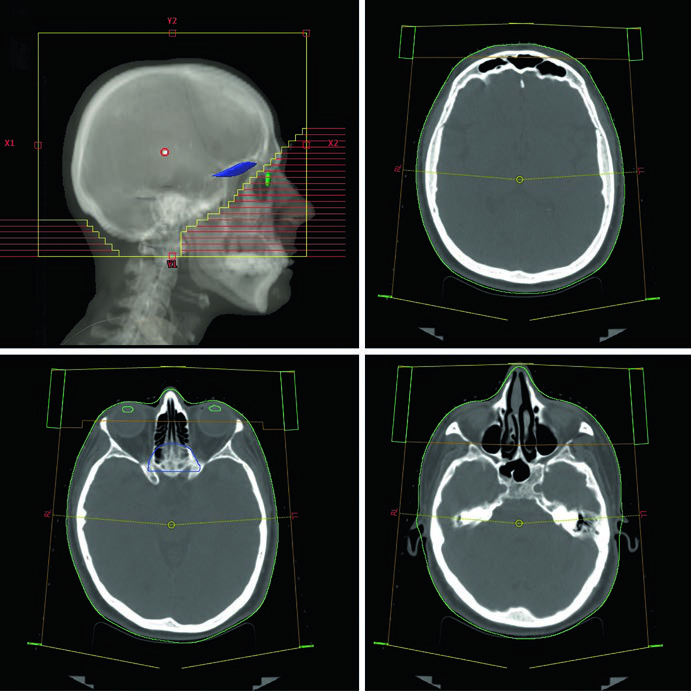

O planejamento da WBRT convencional utiliza 3D-CRT com feixes laterais opostos de fótons de 6 MV. Os feixes são levemente rotacionados em oblíquo anterior direito e esquerdo (RAO/LAO) para evitar divergência nos cristalinos. O colimador multi-lâminas (MLC) bloqueia os cristalinos enquanto cobre adequadamente a placa cribiforme e os lobos temporais. Um detalhe técnico que faz diferença no dia a dia: o isocentro pode ser posicionado na linha média ao nível do canto do olho, eliminando a divergência do feixe para os olhos e cristalinos — uma alternativa prática à rotação dos feixes.

A TC de planejamento sem contraste vai do vértice até a coluna cervical superior, com espessura de corte axial ≤2,5 mm. O paciente fica em decúbito dorsal, cabeça em posição neutra, imobilizado com máscara termoplástica e campo de visão de 600 mm. A verificação de setup usa filmes ortogonais com imagem MV semanalmente na WBRT convencional. O kV diário fica reservado para WBRT baseada em IMRT, onde a precisão de entrega exige verificação mais frequente.

As bordas de campo na WBRT convencional seguem um padrão bem definido: superiormente, 2 cm de flash acima do vértice; posteriormente, 2 cm de flash com possível extensão cervical posterior; inferiormente, base de C1; e anteriormente, o MLC bloqueia desde o flash de 2 cm até a face anterior de C1, protegendo as parótidas e os cristalinos. A cobertura dos lobos temporais e da placa cribiforme é obrigatória em todos os cenários.